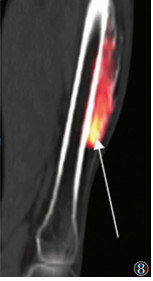

晚期病变21例,X线(21例)、CT(15例)、MRI(11例)及SPECT/CT(15例)阳性率均为100.0%。X线或CT表现为软组织内团状密度增高影,边界清晰,其中9例与相邻骨骼相连,与皮质分界不清,但髓腔不受累。MRI表现为肿块内广泛的T1WI高信号、T2WI低信号(骨化),9例病灶内含T1WI等信号、T2WI高信号、STIR低信号影(脂肪)(图 5)。SEPCT/CT显像15例,其中3例病灶中央及周围均未见显像剂摄取(图 6);6例病灶中央显像剂不均匀摄取(图 7);6例病灶周围显像剂不均匀摄取(图 8)。

| 图 8 男,37岁,右侧股骨前缘骨化性肌炎(晚期)。SPECT/CT矢状位融合图像,显示右侧大腿前侧骨化性肌炎病灶末端显像剂异常摄取(箭头) |

3.3 晚期外伤后5~6个月,肿块开始收缩,周围水肿减轻乃至消失,此期影像学诊断相对容易。X线或CT表现为边界清晰的团块状骨化,可与相邻骨骼相连,与皮质分界不清,但髓腔不受累;MRI表现为肿块内广泛的双低信号,其内可含脂肪信号。但本研究中晚期患者的SPECT/CT特征不一致,可表现为病灶完全无显像剂摄取或病灶中央显像剂高摄取而周围无摄取,也可能表现为中央无显像剂摄取而周围高摄取。提示骨化性肌炎的骨化可能是一个复杂的过程,具体机制有待进一步研究。